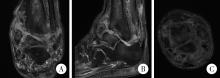

Figure 4

Contrast-enhanced magnetic resonance imaging of the left ankle A, coronal plane; B, sagittal plane; C, axial plane. Contrast-enhanced magnetic resonance imaging demonstrates periarticular soft-tissue edema surrounding the left ankle."